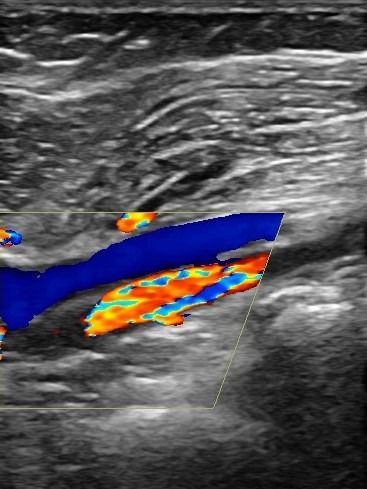

Με το Triplex Αρτηριών Κάτω Άκρων μπορούμε να αξιολογήσουμε αν υπάρχει παθολογία στις αρτηρίες. Συνήθεις παθολογίες στις αρτηρίες είναι τα ανευρύσματα και οι στενώσεις. Με το Triplex μπορούμε να υπολογίσουμε με ακρίβεια το βαθμό στένωσης στις αρτηρίες και να διαπιστώσουμε αν υπάρχει απόφραξη. Η δυνατότητα διάγνωσης παθολογιών στις αρτηρίες των κάτω άκρων με τη χρήση του Triplex είναι πολύ χρήσιμη για την αντιμετώπιση αγγειακών προβλημάτων, καθώς πρόκειται για παθήσεις που μπορούν να οδηγήσουν σε σοβαρές συνέπειες αν δεν ανιχνευθούν έγκαιρα.